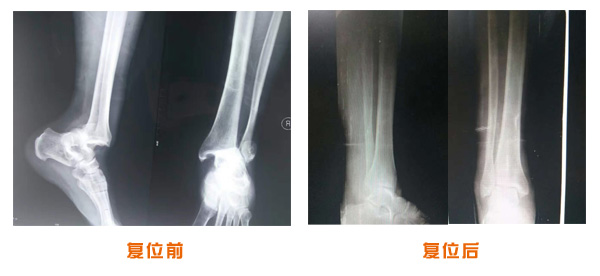

肥城市安駕莊梁氏骨科醫院是一所以梁氏手法正骨配合膏藥為特色的現代化??漆t院。

梁氏骨科術始創于清雍正年間,歷經八代,至今已有三百年歷史。據1929年泰安縣志載“梁瑞圖先生,字增生,號蓮峰,安駕莊人,精岐黃并發(fā)明接骨,凡跌打車凡跌打車軋皮不破而碎骨者......【詳細】 |